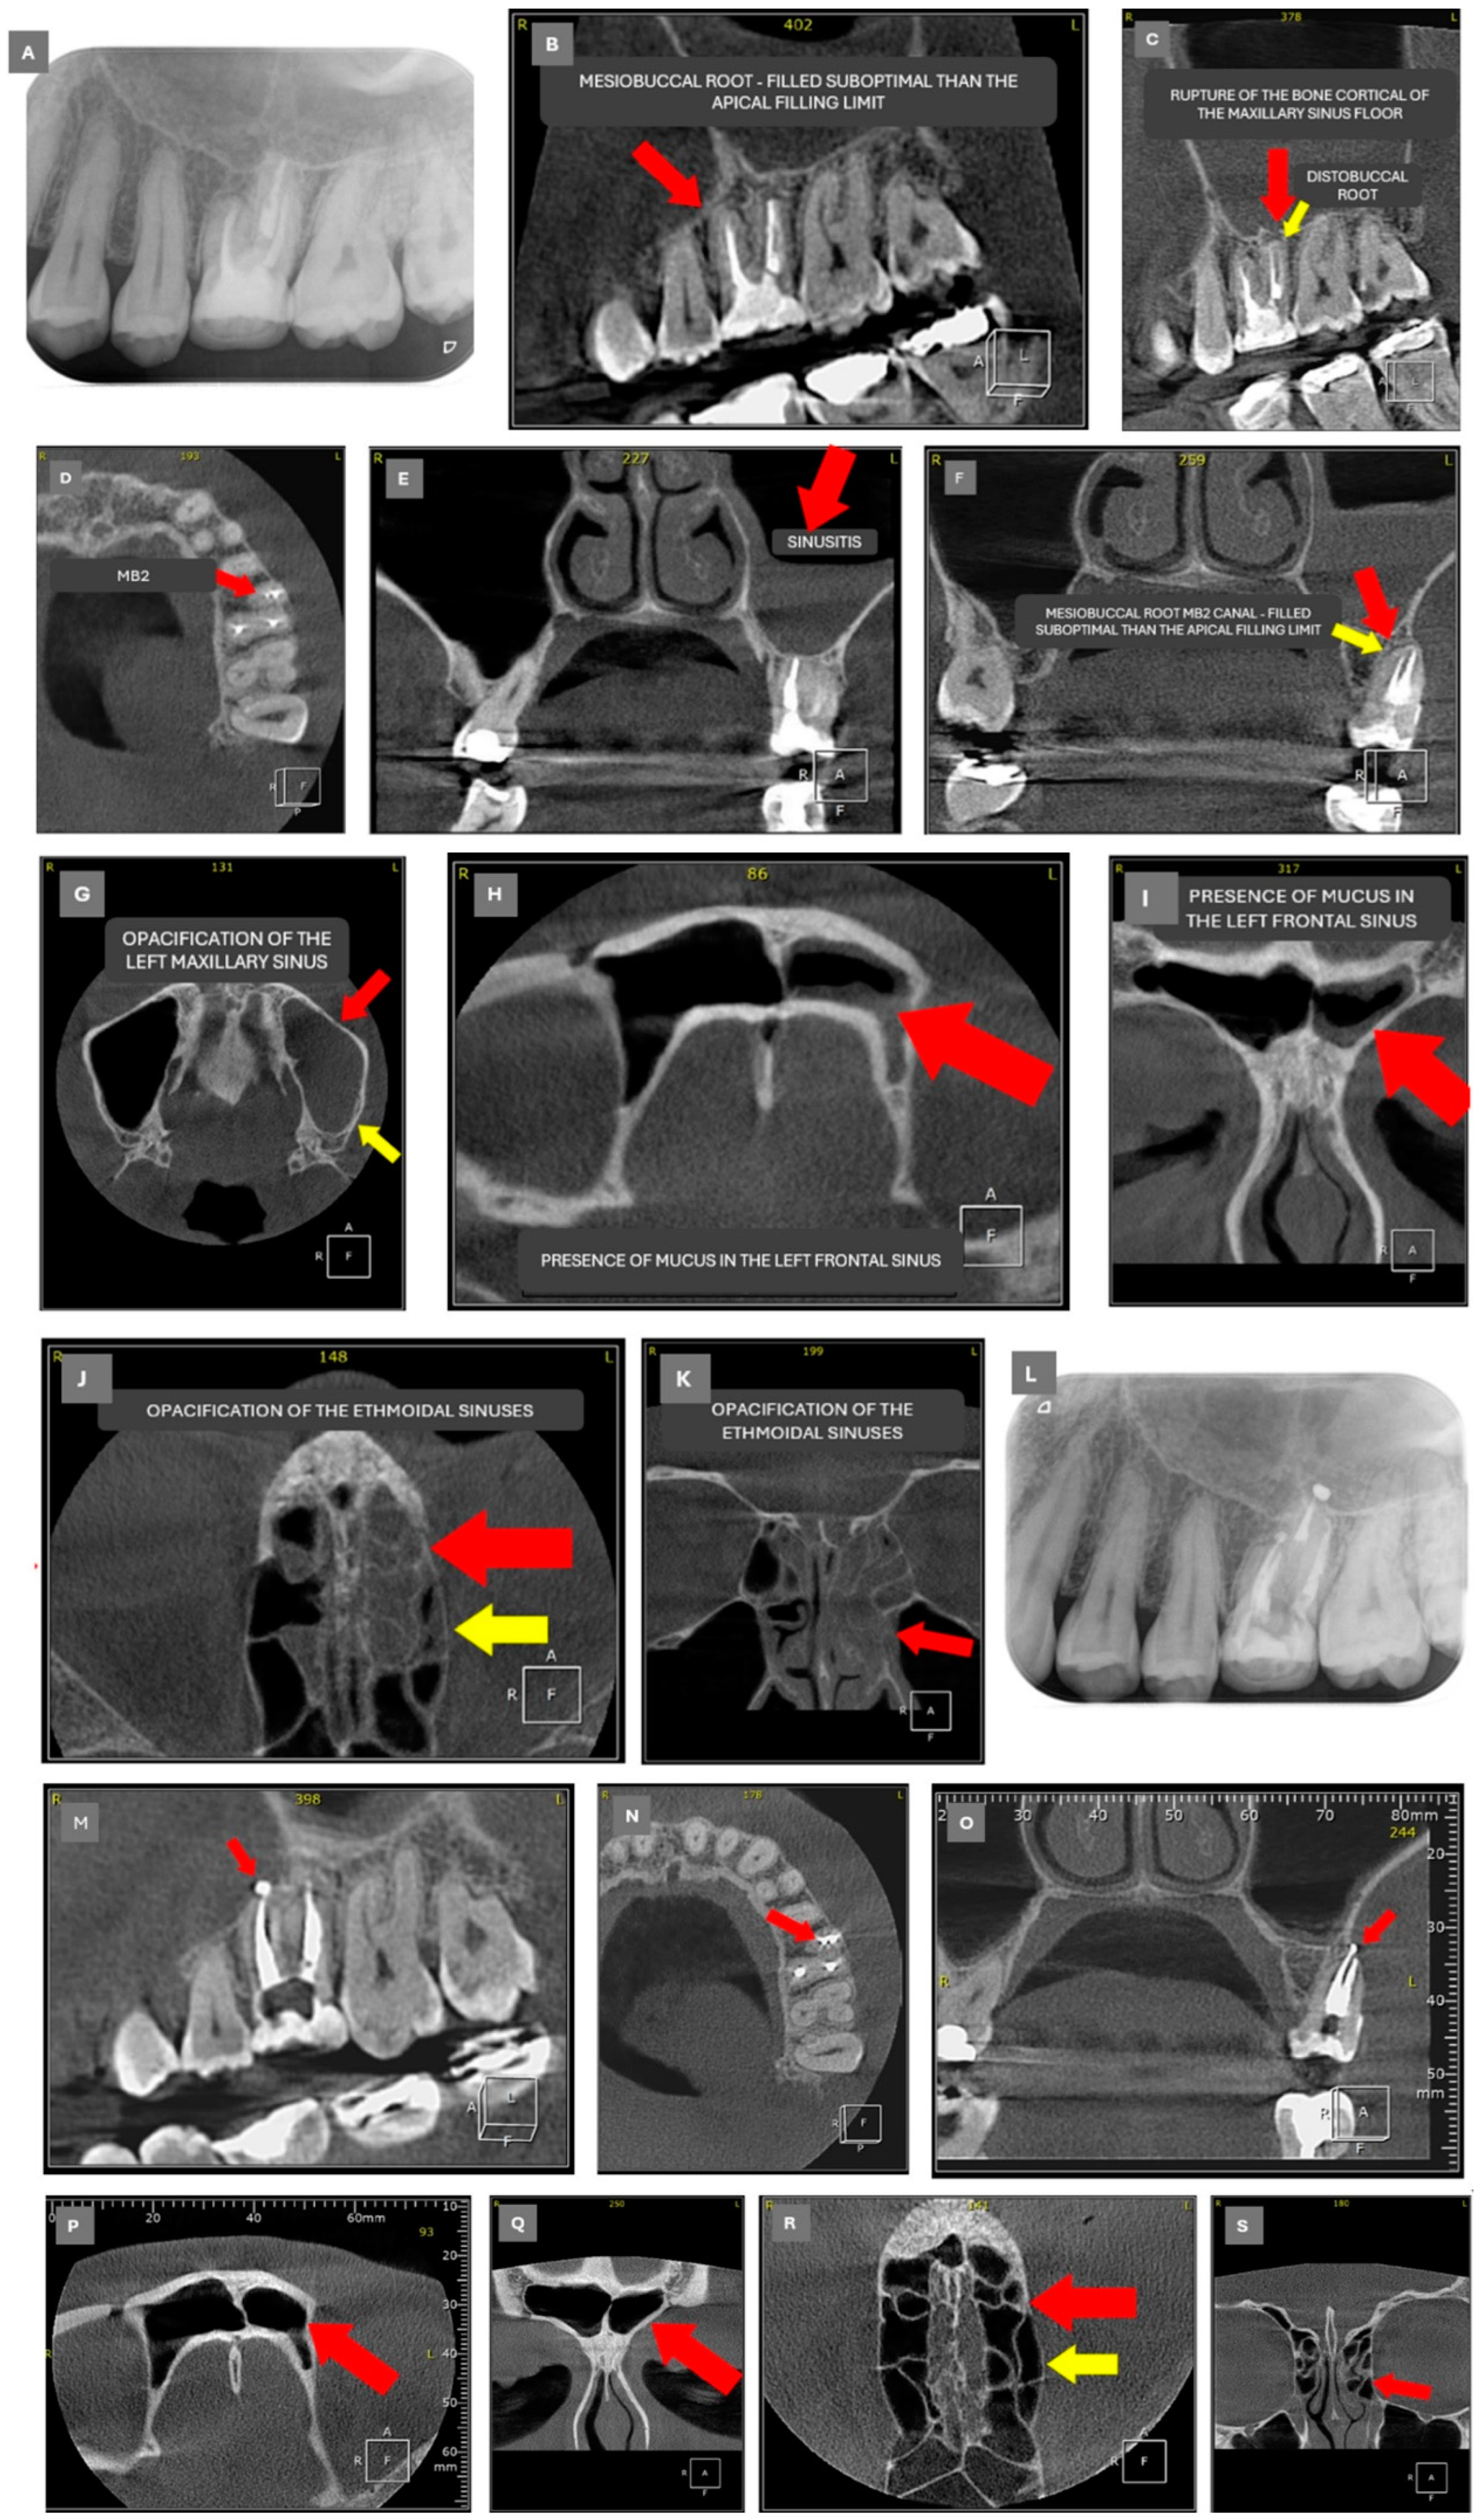

2.2. Case 2